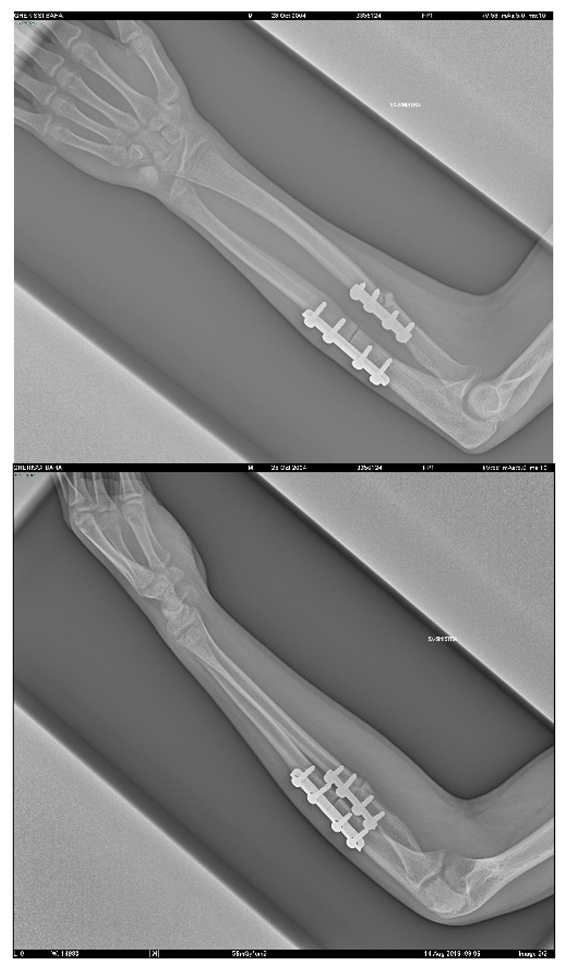

Being able to rely on these tools leads to an improvement in the clinical outcome, lower risks for the patient and reduced post-operative recovery times; the R.X. exam is not performed, with a consequent decrease in the patient’s exposure time to X-rays, plus, the reduction in the timing of the intervention allows a lower anesthetic dose for the patient. This method is particularly advantageous because it allows surgeons to evaluate, before surgery even, which surgical accessories are best suited to the specific anatomical geometry, as shown in the case of femur afflicted with Ollier syndrome. The dimensions of screws, plates and other surgical supports are defined in the catalog and, following the traditional practice, the surgical room must be equipped with a wide variety of tools to be able to meet any need; to be able to decide in advance the dimensions of the screws that realize the desired support allows even more reductions in the times and the risks associated with the intervention, as well as to greatly limit the dimensions in the operating room.

The CASS process was achieved agreeing to the surgeons’ likings and experiences; thus, patients were not consecutive and the study was not randomized. Parents and carers provided authorization for the study. The methodology described and illustrated by the example of a Monteggia lesion has been applied to all the cases reported in Table 4. This resulted in seven different assembly files on CREO, each one representing the phases of the respective surgery. Applying simulation to more than one pathology, involving different body segments, has enabled its effectiveness to be verified and the problems to be solved or improved. Some of the cases have already been operated and the surgeons of Rizzoli were very satisfied with the results obtained in the pre-operative planning phase, finding a considerable reduction in risks and timing during the operating phase.